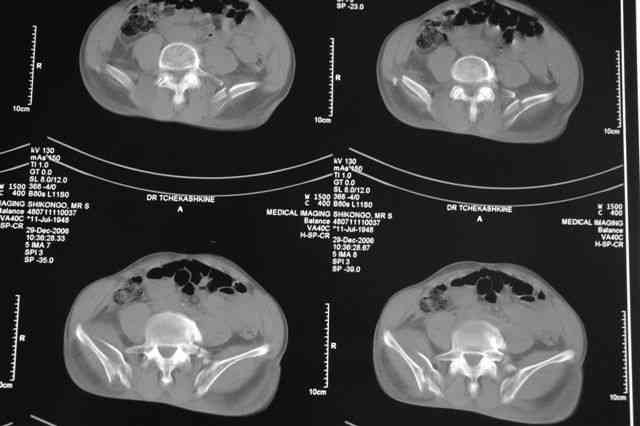

По-поводу фиксации таза спонгиозными винтами. Данный способ все-таки показан для фиксации повреждения крестцово-подвздошного сочленения или переломов крестца. Мне кажется, что в данной случае ситуация иная - имеется перелом "основания" крыла подвздошной кости (в который вовлечена и поверхность, составляющая крестцово-подвздошное сочленение). Не уверен, что фиксация данного повреждения (и заднего полукольца) винтами будет стабильной, так как именно на уровне 1-2 крестцовых позвонков (где обычно вводят винты) линия перелома уходит в латеральном направлении от крестцово-подвздошного сочленения.

Я просмотрел томограммы и у меня создалось впечатление, что винтам есть за что *зацепиться*. В сочетании с 5 мм Шанц винтами, проведенными через нижне-переднюю ость спереди назад через КП сочленения -стабильность тазового кольца должна восстановиться. - Это , конечно, при условии , что закрытая рнепозиция будет успешной.

Травма произошла 22 или 23 декабря, ко мне больной попал 26 декабря, 3 января -остеосинтез перелома бедра и внутр.лодыжки.

после КТ отказался от этой идеи - двусторонний перелом крестца в зоне 1 - алярная часть, при попытке низведения правого гемипелвиса теоретически есть вероятность смещения

фрагмента крестца слева.